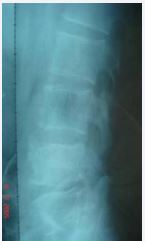

70 patients in this group underwent X-ray, CT, MRI and Dual energy X-ray Absorptiometry (DXA) examinations. X-ray films showed 57 cases (81.42%) of patients with narrow intervertebral space and irregular bone destruction at the edge of the vertebral body (Figure 2),

Figure 2 Brucellosis at L3-5. X-ray showed multifocal, wormlike or saw-like destruction of bone at the edge of the vertebral body, clear and sharp lesion edges with soft tissue density, narrow intervertebral space, increased density, irregular appearance of upper and lower vertebrae, with a tendency of bone destruction and no dead bone.

In 13 patients (18.57%), the bone at the edge of the vertebral body was stiffened like a bird’s beak, which was connected with the edge of adjacent vertebral body hyperplasia to form a bone bridge, and 11 patients (15.71%) had poor lumbar stability. CT showed 53 cases (75.71%) patients with vertebral edge disease have size about 2~6 mm multiple focal bone destruction, bone destruction around focal sclerosis of bone hyperplasia, bone of new born stove and new bone broken, the whole edge vertebral bodies like lace structure formation “lace vertebral (Figure 3)”; In 17 cases (24.28%), intervertebral disc lesions showed isodense shadows, articular cartilage surface sclerosis and hyperplasia, proliferated bony protruding toward the edge of the vertebral body to form “lip”-shaped osteophytes, anterior longitudinal ligament and paravertebral sides were calcified, and there were osteophytes connect (Figure 4); In this group, 18 patients (25.71%) had widened paravertebral muscles with abscess formation and clear surrounding space, but no abscess drainage imaging (Figure 5).

Imaging examination Early X-ray films only showed lumbar degeneration and vertebral osteoporosis, no spinal infection, and generally changed after 6 to 8 weeks of onset. Once X-ray signs appeared, they developed rapidly, and the vertebral body Marginal bone destruction and intervertebral space stenosis mainly, bone destruction concentrated on the upper or lower edge of the vertebral body, manifested as progressive intervertebral space stenosis, involving two adjacent vertebral bodies, and may be accompanied by destruction of intervertebral facet joints Caused spinal instability, but no vertebral body compression or wedge-shaped deformation, bone bridge was shown in the later stage, extremely sclerotic, but rarely bony fusion, 53 cases in this group showed narrow intervertebral space, vertebral edge bone destruction, 17 cases of vertebral body Marginal bone hyperplasia forms a bone bridge; CT examination can clearly show the degree of bone destruction in the lesion, whether there is a cavity and paravertebral abscess formation, the intervertebral disc is destroyed as an isodensity shadow, the pedicle is not destroyed, and the periosteum at the edge of the vertebral body is hypertrophic and calcified due to inflammation stimulation, forming a “lip-like” Osteophytes, new bone at the edge of the vertebral body interlaced with small destructive foci to form “lace vertebrae”, “lip-shaped” osteophytes and “lace vertebrae” constitute the characteristic manifestations of BS, and CT is unique in showing paravertebral abscesses around the lesion.